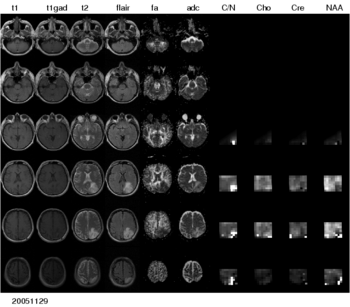

Figure 1: Multi-modal image data from a patient with low-grade glioma. A large number of different modalities and derived parameter volumes are acquired during the monitoring of tumor growth.